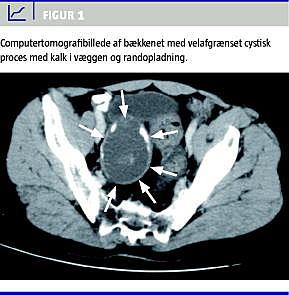

En tidligere rask 60-årig mand søgte læge pga. nedre abdominale smerter, tenesmi ved endetarmen og nyopstået hæmorideproblematik. Egen læge palperede ved rektaleksploration en glat udfyldning i det lille bækken og udførte herefter rektoskopi, der viste normale forhold. Patienten blev henvist til ambulant vurdering på en kirurgisk afdeling, hvor palpationsfundet blev bekræftet. Der blev fundet normale forhold ved koloskopi. Herefter blev der foretaget CT og efterfølgende også magnetisk resonans-skanning, hvor der blev påvist en 13 × 5,5 × 5 cm stor, velafgrænset, cystisk forandring beliggende i højre side af bækkenet (Figur 1 ). Udgangspunktet for processen kunne ikke identificeres. Der var ingen tegn til invasiv vækst. Ved laparotomi fandt man et stort appendixmukocele adhærent ned i fossa rectovesicale. Mukocelet blev fjernet in toto, og basis af appendix blev delt med gastrointestinal anastomose-stapler. Patologien var mucinøst cystadenom med fri resektionsrand.

Symptomerne ved appendixmukoceler er meget varierende og uspecifikke, og tilstanden opdages ofte tilfældigt [1]. Som illustreret i denne sygehistorie er det ofte ikke muligt at stille diagnosen præoperativt [1], selvom der er fundet karakteristiske forandringer ved CT [2]. Det karakteristiske fund er en cystisk forandring, hvor der kan være vægforkalkninger. Associa-tionen til caecum kan ikke altid påvises. Det er væsentligt, at diagnosen stilles, og at mukocelet fjernes, idet lidelsen kan være malign. Desuden kan spontan ruptur føre til pseudomyxoma peritonei, der er en potentielt dødelig tilstand [3]. Ved operativ fjernelse af mukoceler er det vigtigt, at der ikke opstår perforation, da en sådan kan være årsag til senere pseudomyksomdannelse [4]. Af denne grund anbefales også åben appendektomi, når tilstanden er erkendt [5]. Man må fraråde finnålsaspiration, hvis der er mistanke om mukocele, og denne sygehistorie viser, at man i tilfælde med cystiske intraabdominale processer bør være tilbageholdende med at nålebioptere. Hos kvinder og børn vil der være flere differentialdiagnoser (ovariecyster og kongenitte misdannelser), hvor finnålsaspiration i visse tilfælde udføres. Vi anbefaler derfor, at man hos disse patientgrupper undlader aspiration, hvis en cystisk proces kan have relation til caecum, eller hvis der er forkalkninger i væggen. Sygehistorien viser også, at vigtig patologi kan afsløres i almen praksis ved simpel rektaleksploration.